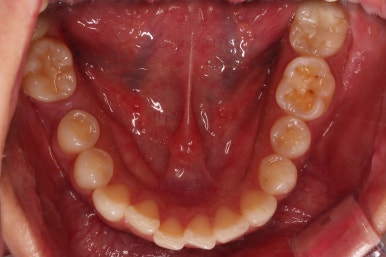

1. 초진

연산동교정치과 초진 시 입안의 모습입니다.

얼핏 앞에서 봤을 때 치열이 나쁘지 않아 보이는데요.

대신 자세히 살펴보면 윗니 양쪽 송곳니가 덧니처럼 볼록 튀어나와 있고요.

아랫니 어금니가 하나 없어서 주위 치아들이 해당 위치로 쓰러진 상태였습니다.

그리고 양쪽의 교합이 톱니바퀴처럼 맞물려 있는 것 같지만 톱니바퀴가 한 칸씩 밀려서 맞물려 있는 부정교합이 있는 상태였습니다.